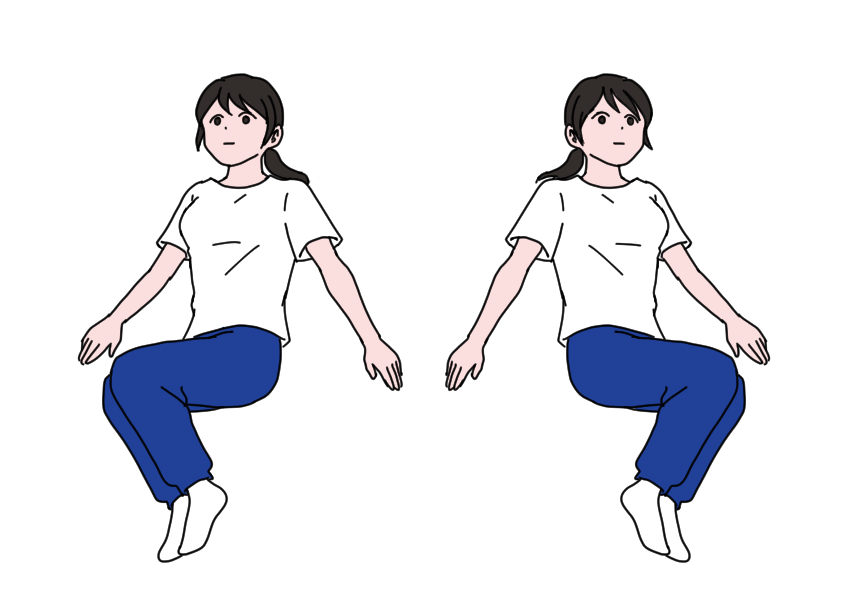

- 仰向けで膝を立て、左右の膝を小さく倒す動きをゆっくり繰り返すことにより、骨盤まわりの緊張をゆるめ仙腸関節の動きをなめらかにする。

仙腸関節は強いストレッチで悪化することがあるため、軽い動きで固まった骨盤のまわりをリラックスさせることが大切です。